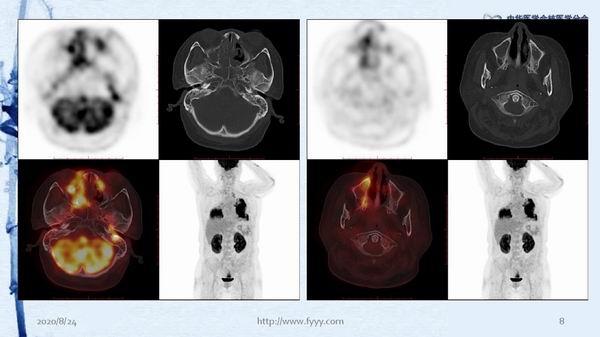

病例82:肉芽肿性血管炎PET-CT显像一例-【CSNM继教学组】郑山 福建医科大学附属第一医院